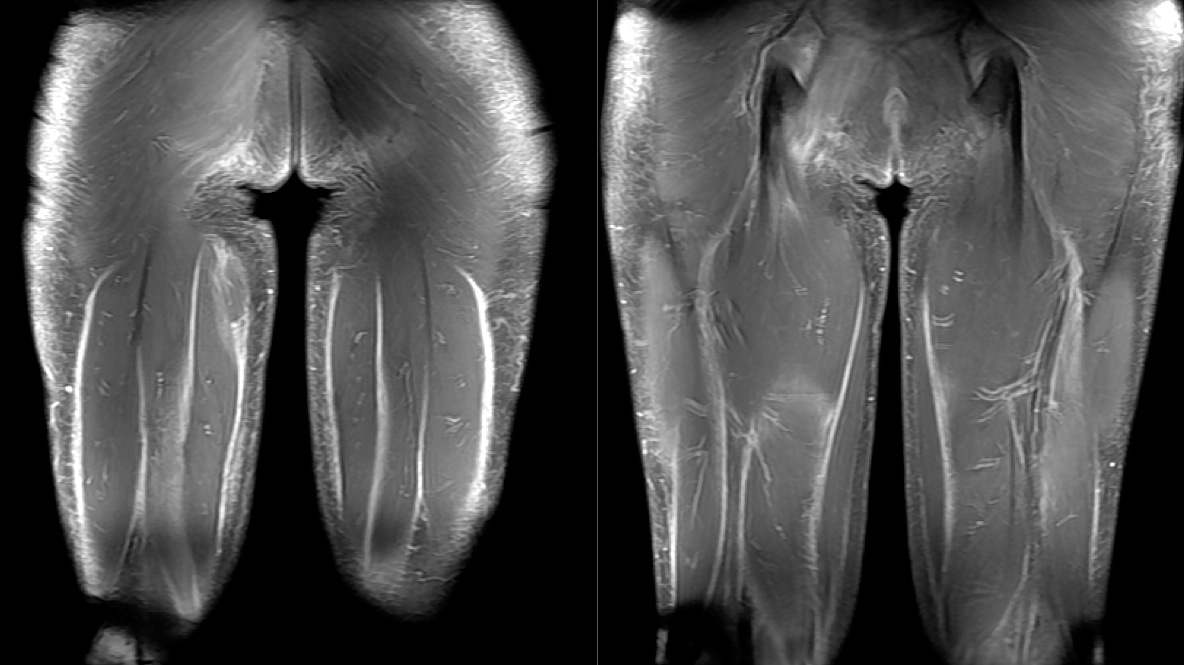

Figure 3 for case Systemic sclerosis with diffuse fascitiis

Figure 3